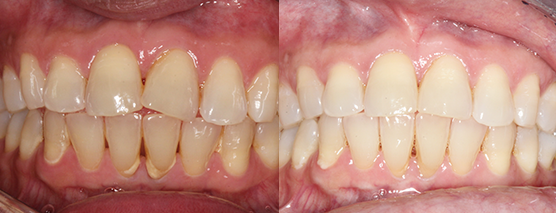

Case examples that can be treated in your practice.

(Cases treated by Dr Andrew Chang using in office aligner solutions)

Before

After